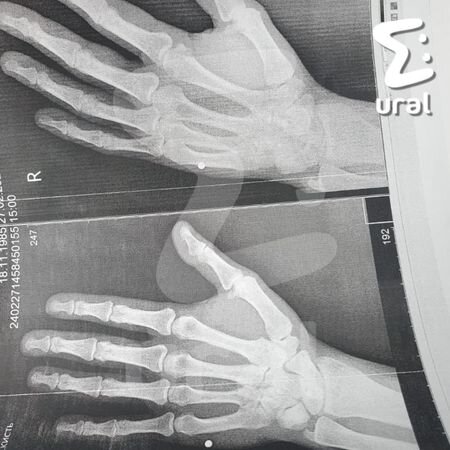

Таксист прострелил руку пермяку за то, что тот очень торопился домой на обед.

Классовое противостояние на дороге началось, когда бомбила Владимир подрезал очень быстрого и голодного инженера Алексея. Таксист выругался, пообещал выбить торопыге все зубы.

Инженер уверенно пошёл к машине — Владимир приоткрыл стекло, просунул туда пневмат и дважды выстрелил мимо. Алексей достал перцовку, залил автохама и в этот момент получил пулю в ладонь. Дорожный конфликт теперь разбирает полиция.